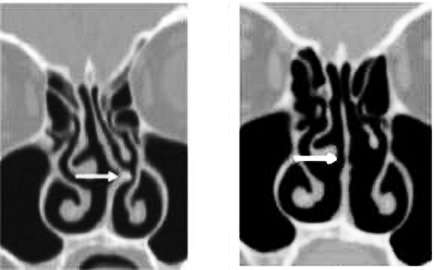

Schematyczne przykłady

skrzywień przegrody nosa w prawo. Dla pacjenta objawy w obydwu

przypadkach mogą być takie same - m.in. gorsze oddychanie prawą stroną

nosa. W pierwszym przypadku trzeba jednak wykonać klasyczny zabieg,

natomiast w drugim można przeprowadzić zabieg laserowy (kolec przegrody

nosa widoczny też na zdjęciu)

Stan przed i po klasycznym zabiegu operacji skrzywionej przegrody nosa:

schemat i obraz z tomografii komputerowej